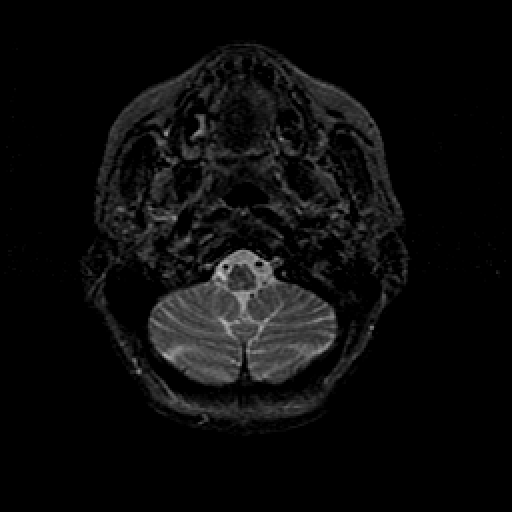

T2-weighted structural MR: Slice 7

Slice 7